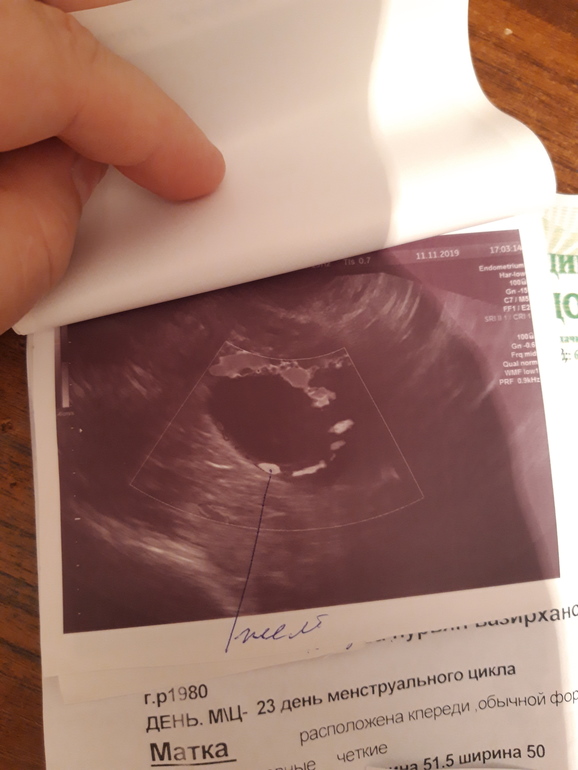

Врач увидела вот это образование,размером 25,не знает она что это,фолликул или жт,в позадиматочном пространстве не значительное количество жидкости,эндометрий 13,а правый яичник она норм и не увидела,а правая сторона нормально так тянет,в общем кто разбирается,это фолликул или же жт? И бывает ли кровоток у доминантного фолликула?

На последнем снимке фоликул. Желтое тело имеет другую структуру. И при фоликуле часто бывает жидкость в позадиматочном пространстве, в маленьком совсем количестве. Когда фолик лопается, там уже жидкости много